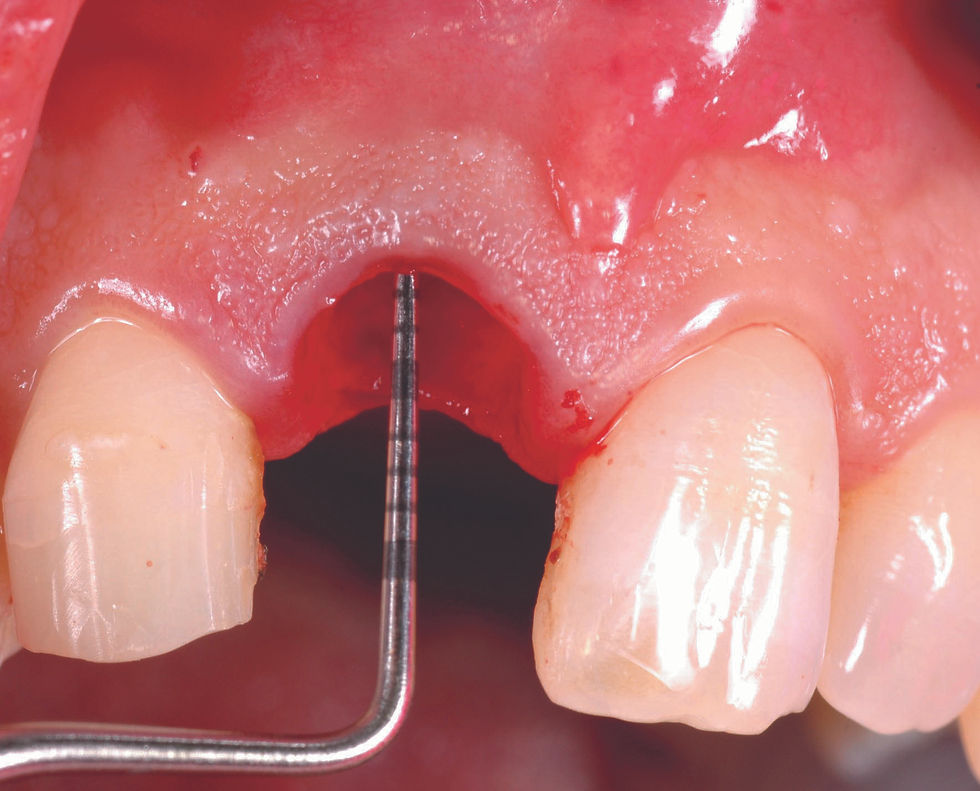

Initial clinical situation.

Atraumatic extraction of the fractured element is performed together with the debridement of the alveolus.

Probing of the residual bone crest, that detects a partial lack of the vestibular bone wall.